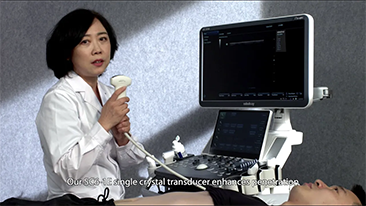

Moins de stĂŠthoscope, plus d'ĂŠchographie??

L'optimisation des flux de travail en gynÊcologie et obstÊtrique est indispensable pour traiter les volumes importants de patientes se prÊsentant pour des dÊpistages. Par exemple, les malformations du système nerveux central (SNC) font partie des anomalies congÊnitales les plus frÊquentes. Compte tenu des diffÊrentes conditions dans lesquelles sont rÊalisÊes les Êchographies, par exemple lorsque le f?tus est mal positionnÊ, il est particulièrement difficile de visualiser le plan transcÊrÊbelleux sur les Êchographies 2D. L'automatisation de la dÊtection et de la prise de mesures peut donc grandement amÊliorer l'efficacitÊ de l'imagerie.